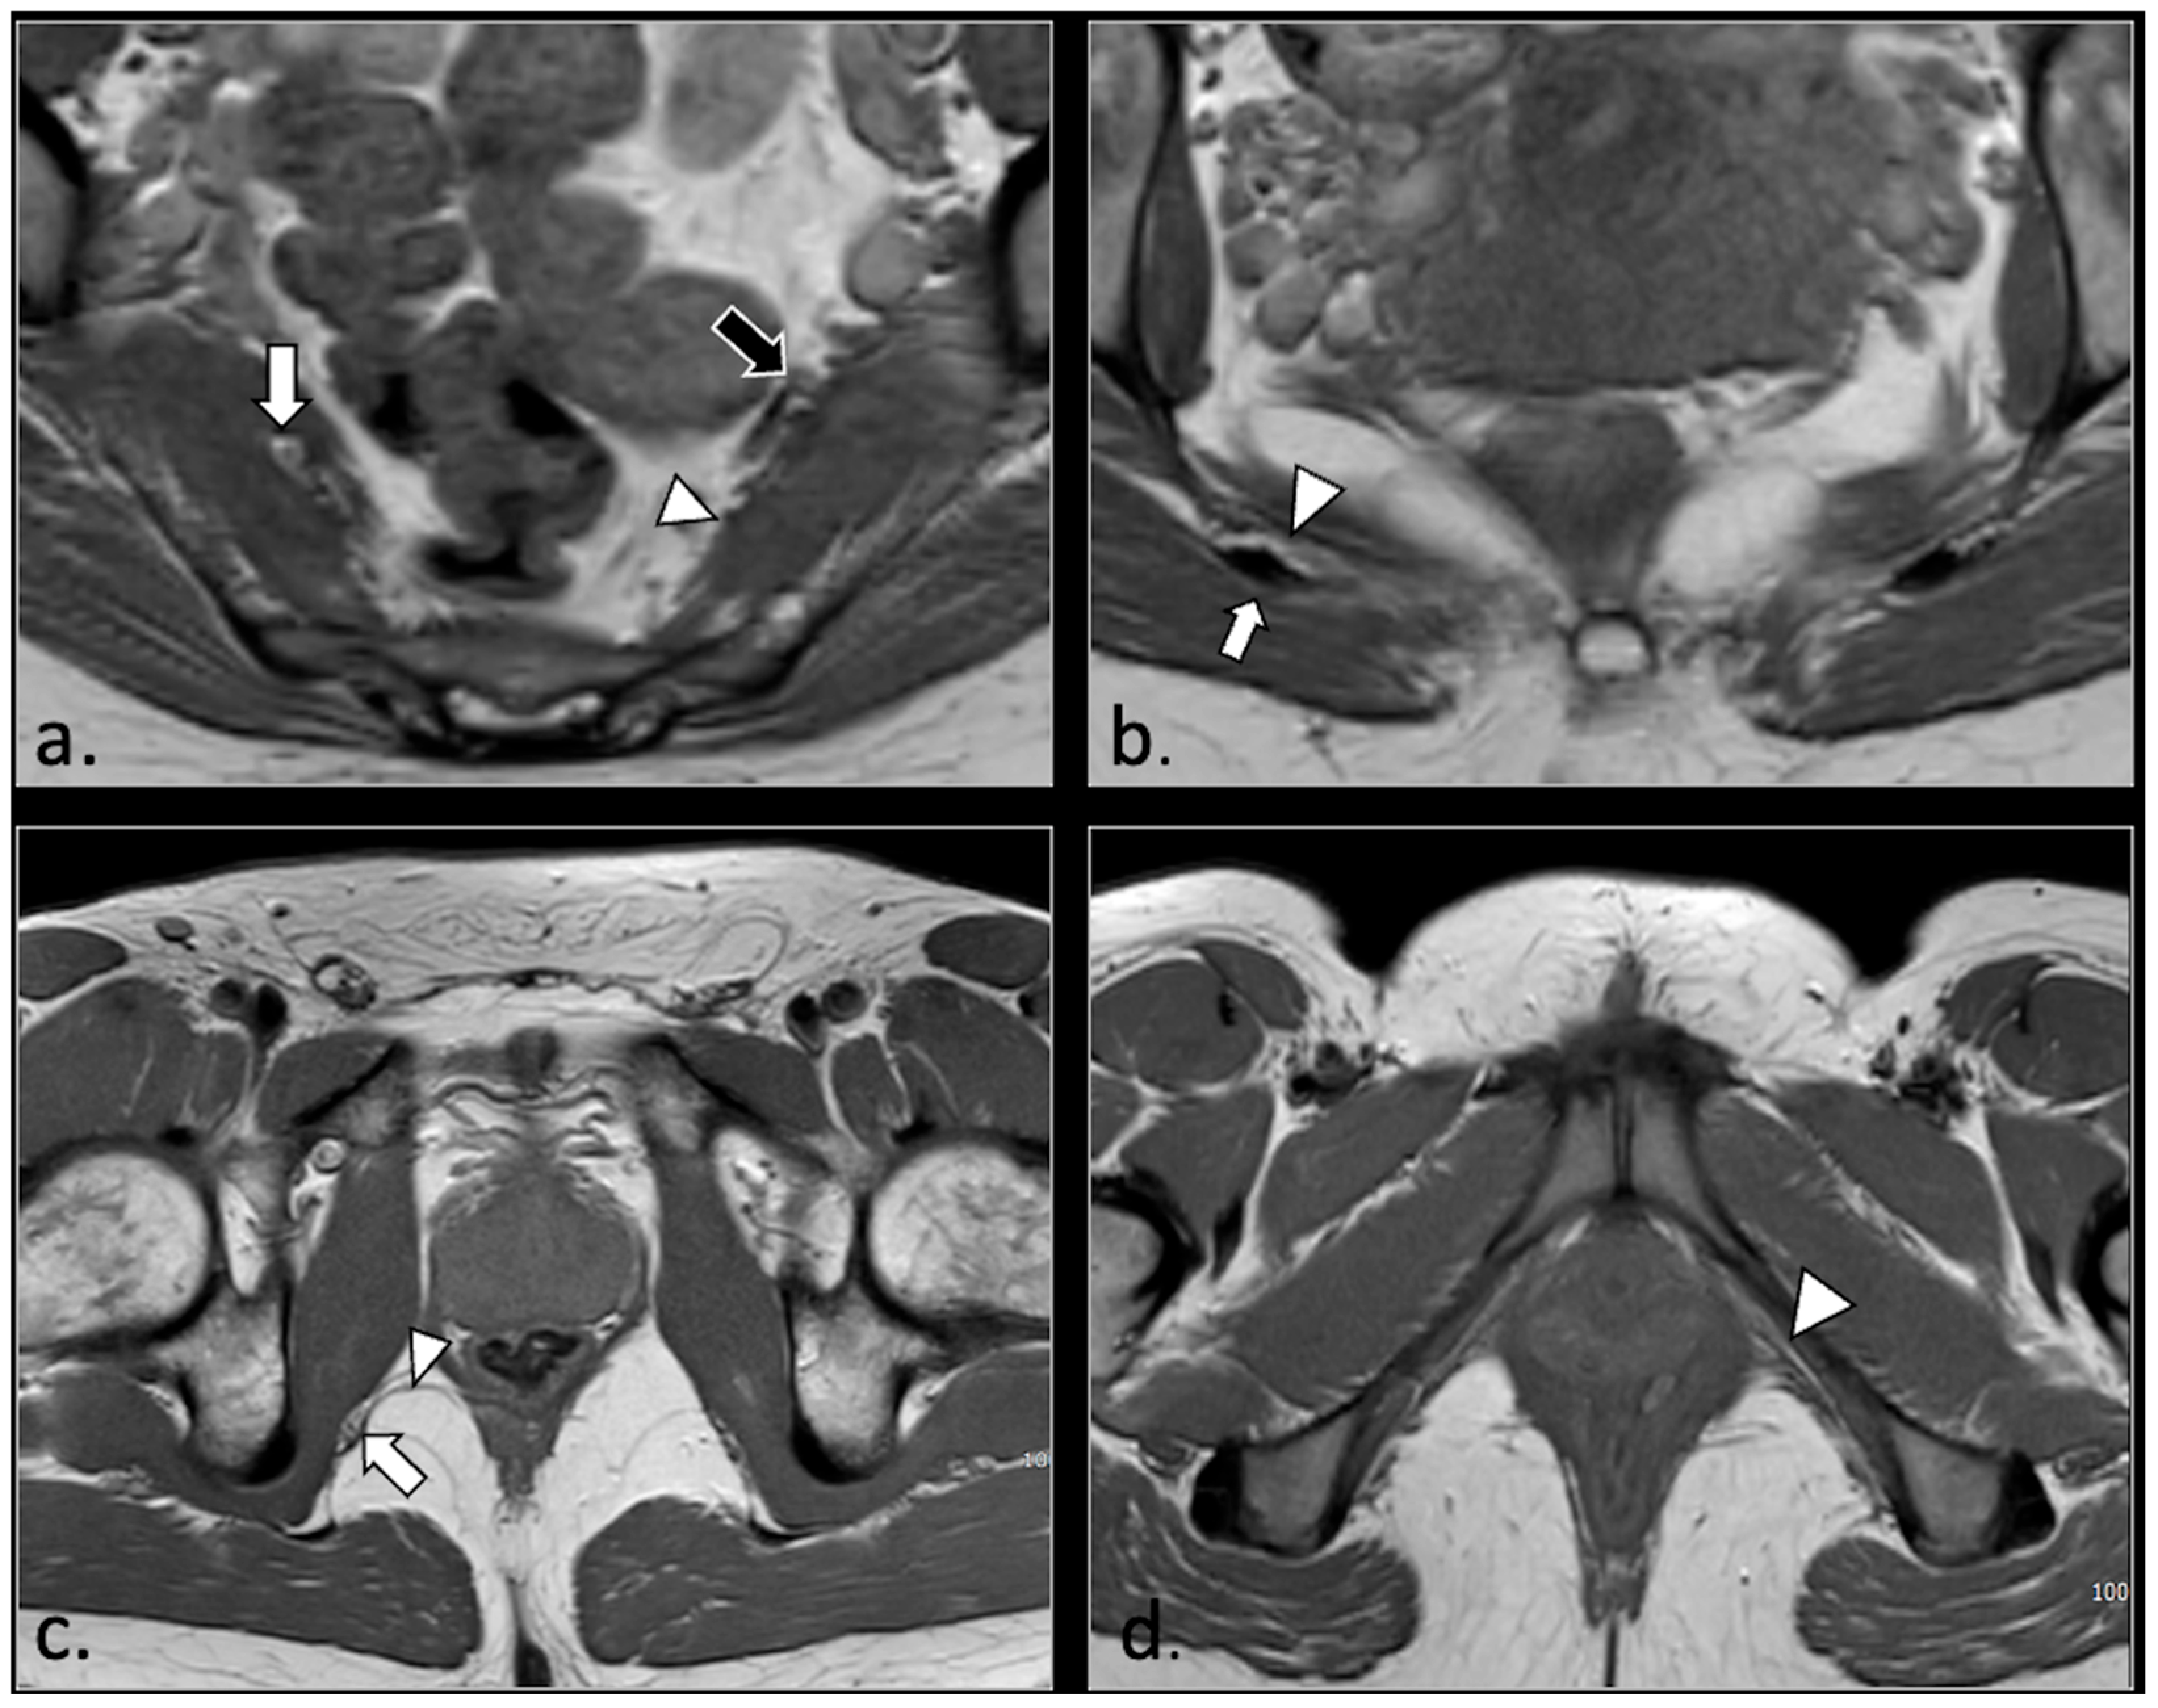

- Unilateral or bilateral hypertrophy of the pyriform muscle (4 patients);

- Unilateral or bilateral lesions of the sacrotuberous and/or sacrospinous ligaments (interligamentous space) (5 patients);

- Unilateral rupture of puborectal and/or pubococcygeal muscle (4 patients);

- Perineal fibrosis involving Alcok’s canal (4 patients);